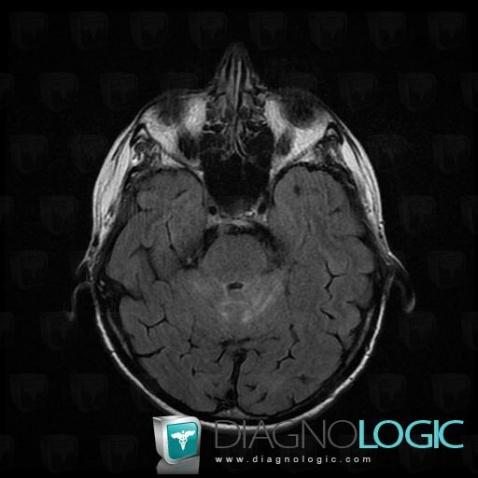

Les images ci-dessous illustrent ce dossier pour les diagnostics Carcinose méningée, Méningite carcinomateuse, pour les modalités (IRM)

Voici les informations spécifiques à l'image clé ci dessus:

- Diagnostic Méningite carcinomateuse, Localisation(s) Région cortico sous corticale, comportant les gammes Lésion sous corticale